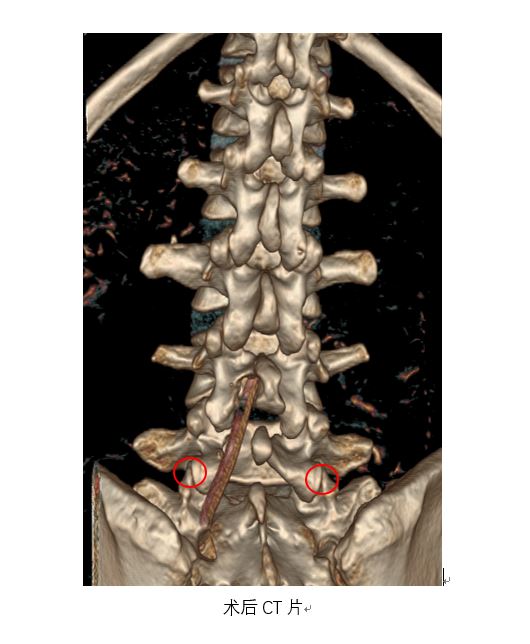

术中,赵杰主任带领手术团队,在为患者置入椎间孔镜时采用了腰椎后路微创手术切口同一入路,不给患者增加新的手术切口,不破坏关节突关节等脊柱结构,不广泛剥离椎旁肌软组织,不进行椎间融合钉棒固定,充分保证了患者要求的较高术后生活质量,巧妙实现了对正常骨结构的保护和对肿瘤的精准彻底切除。整个手术过程,骨科团队和神经外科团队配合流畅,术中神经电生理监测正常。

术后影像学提示患者关节突关节等骨性结构完整,术后病理回报肿瘤切缘干净,肿瘤切除彻底。患者腰腿痛症状明显改善,足部麻木感缓解。